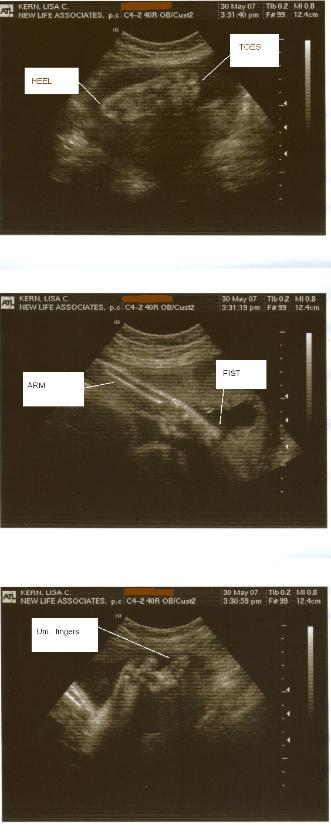

5-30-07

We finally had an ultrasound!!  If you want to

click here.  Otherwise, the

baby is looking just fine.  We're within three

days of our due date, size-wise, so that's good

arrives!  Here are some more baby pictures.

There are also pictures on the page linked

above, but only click that if you want to know

the sex!

Click here for the video of the

ultrasound.